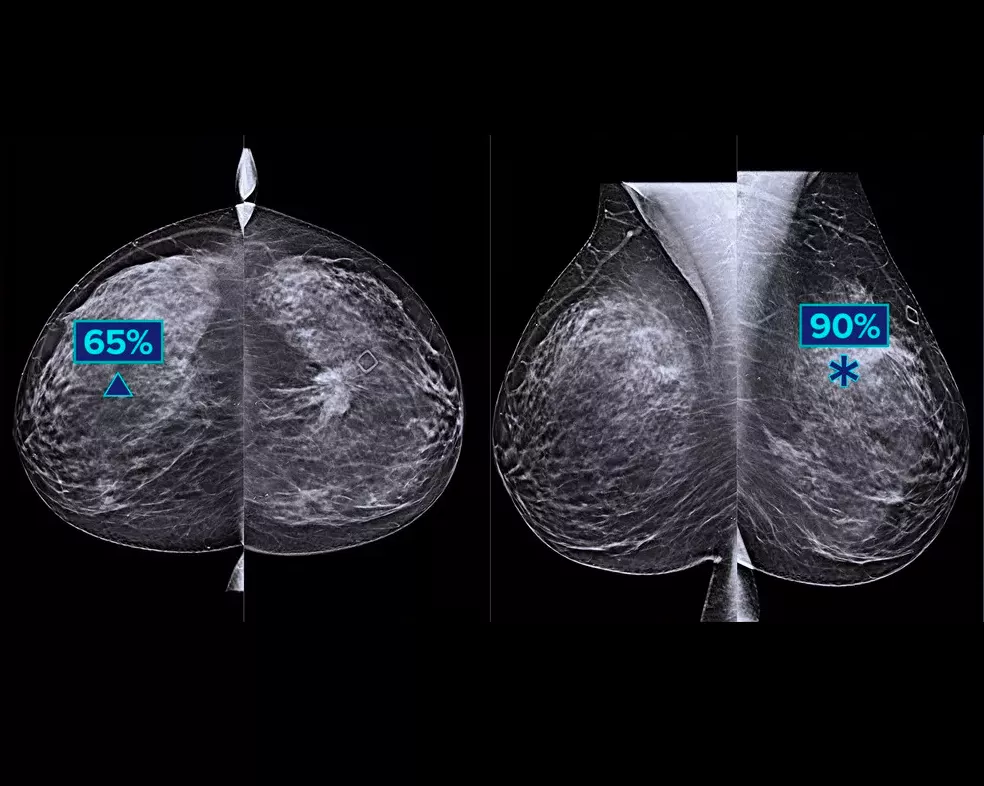

Study shows +9% improvement in observed reader sensitivity for cancer cases.1.2 Works on standard and high-resolution tomosynthesis images; overlay on 3DQuorum SmartSlices and synthesised 2D images.

The algorithm looks for 3 main groups of suspicious lesions: calcifications, masses, densities and distortions, and any combination of these lesions. Outputs may vary on different reading workstations.

Hologic conducted a multi-reader, multi-case (MRMC) study to verify performance when using Genius AI Detection algorithm.3